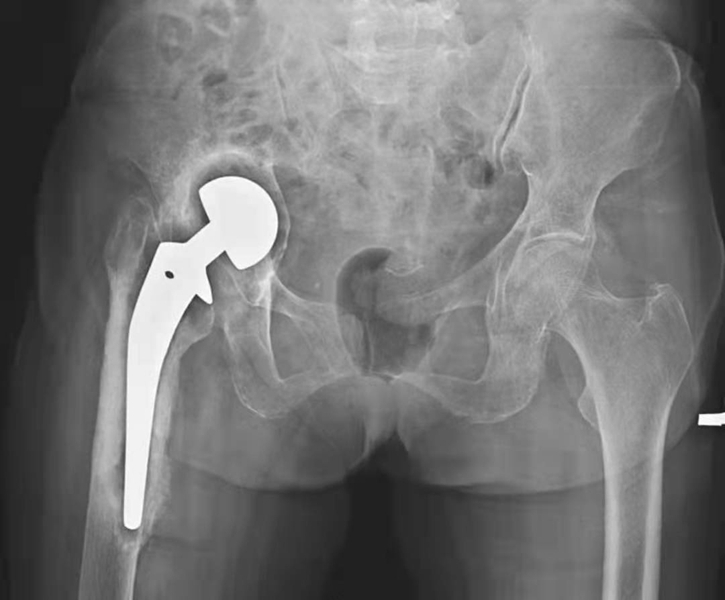

一、无菌性松动

大多数松动发生在假体柄和骨水泥之间间隙,偶然发生在髋臼帽与骨水泥之间。无菌性松动的诊断,应包括临床松动和X线松动。临床松动诊断主要根据大腿和髋部疼痛等症状。X线松动主要有以下征象:①假体周围透亮带超过2mm,且有持续增宽趋势。②假体移位下沉或旋转等超过4mm(图2,图3);③关节造影同时行牵引见造影剂向假体与骨界面渗入,仅据其中一项即可诊断。